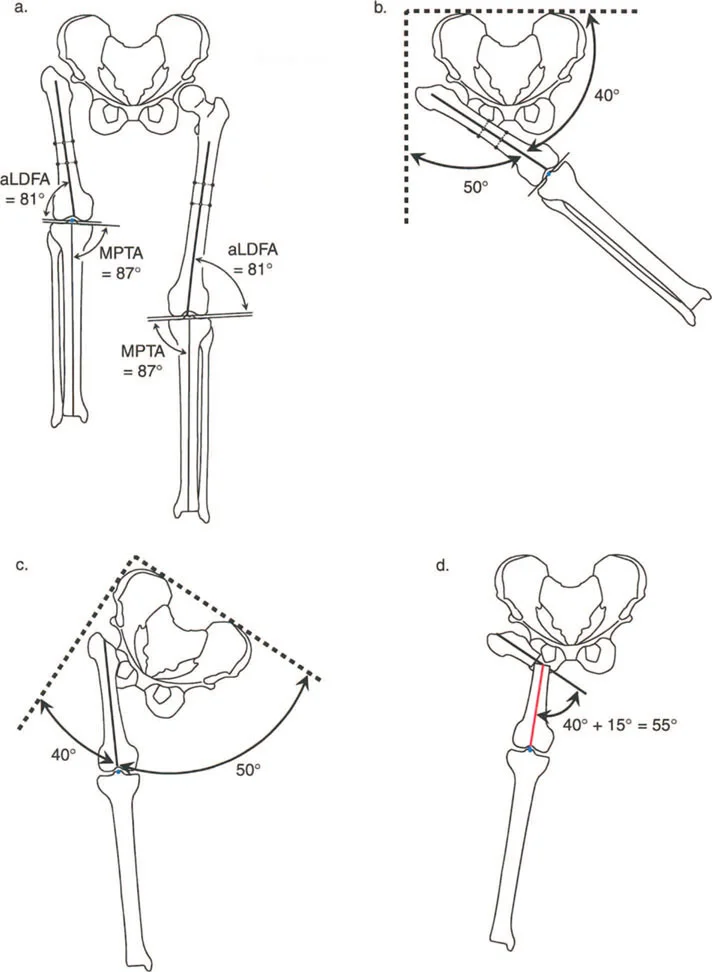

الزوايا الهامة في تقييم الورك

يستخدم جراحو العظام عدة زوايا لقياس محاذاة مفصل الورك وعظم الفخذ، وهي حاسمة في تشخيص التشوهات وتخطيط العلاج:

- الزاوية بين عنق وجسم الفخذ (Neck-Shaft Angle - NSA): هي الزاوية بين محور عنق الفخذ ومحور جسم الفخذ.

- الزاوية الطبيعية: تتراوح عادة بين 125° و 135°.

- كسع الورك (Coxa Vara): تحدث عندما تكون هذه الزاوية أقل من الطبيعي (أقل من 120°)، مما يجعل عنق الفخذ أكثر أفقية.

- فحج الورك (Coxa Valga): تحدث عندما تكون هذه الزاوية أكبر من الطبيعي (أكثر من 140°)، مما يجعل عنق الفخذ أكثر عمودية.

- الزاوية الميكانيكية لعظم الفخذ القريب (Mechanical Proximal Femoral Angle - MPFA): تقيس العلاقة بين محور عظم الفخذ ومستوى المدور الكبير.

- الزاوية الجانبية لعظم الفخذ القريب (Lateral Proximal Femoral Angle - LPFA): تقيس ميل الجزء العلوي من عظم الفخذ.

تؤثر هذه الزوايا بشكل مباشر على ميكانيكا مفصل الورك، وخاصة على ذراع الرافعة للعضلات المبعدة للورك. عندما تكون هذه الزوايا غير طبيعية، يزداد الضغط على المفصل، وتضعف العضلات، مما يؤدي إلى الألم والعرج وتآكل المفصل.

تعتبر الأشعة السينية (X-rays) هي الأداة التشخيصية الأساسية والأكثر أهمية في تقييم تشوهات مفصل الورك. يتم أخذ صور متعددة للمفصل من زوايا مختلفة (مثل الأمامي الخلفي والجانبي) لتمكين الجراح من:

- قياس الزوايا: تحديد الزاوية بين عنق وجسم الفخذ (NSA)، والزاوية الميكانيكية لعظم الفخذ القريب (MPFA)، والزاوية الجانبية لعظم الفخذ القريب (LPFA). هذه القياسات حاسمة لتخطيط الجراحة.

- تقييم شكل العظام: تحديد وجود كسع الورك أو فحج الورك، أو تضخم المدور الكبير، أو رأس فخذ بيضاوي الشكل.

- الورك الفاروسي مع المدور الكبير المتضخم: في هذه الحالات، يكون التشوه ناتجًا جزئيًا عن عنق الفخذ وجزئيًا عن تضخم المدور. يتطلب التصحيح الجراحي عادةً قطع عظم فحجي (Valgus Osteotomy) مع نقل للمدور الكبير.

- تشوه فحجي مع دوران داخلي لعظم الفخذ القريب وخلع جزئي للورك: قد يتطلب هذا قطع عظم فاروسي مع إزاحة وسطية ونقل المدور الكبير للأسفل والجانب.